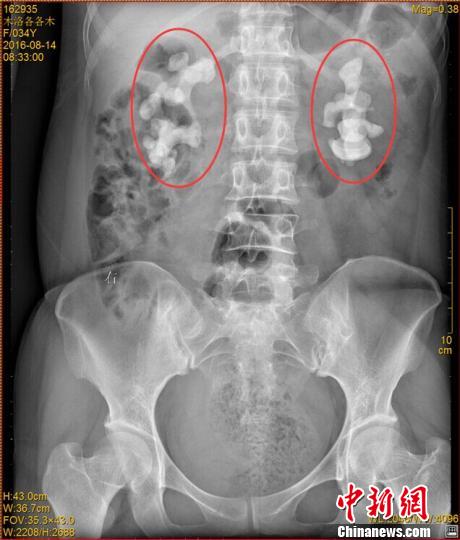

各各木术前影像图片,红圈内为巨大肾结石。 钟欣 摄

中新网成都11月7日电 (王鹏)记者7日从四川省结石病医院获悉,该医院近日收治了一名罕见肾结石病人。来自四川凉山的34岁女子各各木,双肾长出10厘米巨型结石,肾内空间几乎全被结石填满。

“临床上,双肾长巨大结石的患者一般都是中老年男性,女性较为少见,年轻女性更加罕见。”四川省结石病医院常立高医生详细检查后发现,该女子双肾内空间几乎被结石全部填满。他询问患者后判断,该罕见病例的出现与女子常年喝生水有直接关系。